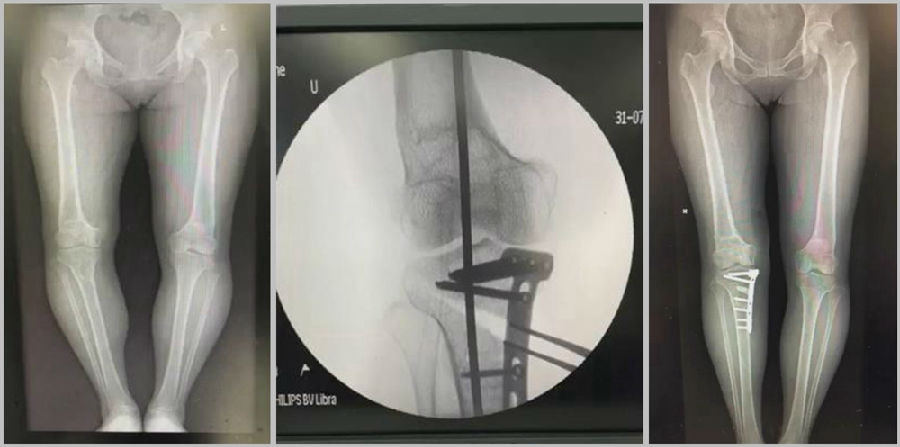

1、综合判断力线的方法

现在对于力线的判断大致通过以下几方面:①大体形态;②透视确定力线,连接股骨头中心、踝关节中心,看力线杆和膝关节中心的位置关系;③MPTA(胫骨平台关节线和胫骨侧机械轴夹角);④PSI。

(1)肢体外旋

一般来说在麻醉状态下肢体会处于外旋位,此时去测定力线的话往往需要将肢体放在旋转中立位,但是在内旋肢体的过程中会出现内翻应力,那么这种情况下判断力线会带来误差,所以通常建议大家要把手术床做一点旋转,让患肢处于自然的旋转中立位,这样再去判断力线就比较准确。

(3)力线验证未模仿负重应力

现在所谓的目标力线应该是模仿负重时的力线。做截骨时,通常会将力线轻度外移,如果没有考虑关节内畸形、韧带松弛或是软骨磨损,那么在负重时,在内侧副韧带撑开过程中,会出现力线偏移。所以要注意,手术中间在调整目标力线时,要以应力状态下为标准。